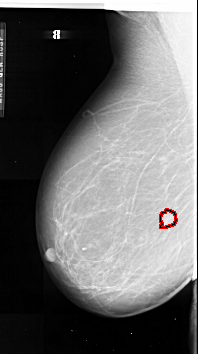

A_1090_1.LEFT_MLO

LEFT_MLO LINES 6361 PIXELS_PER_LINE 3556 BITS_PER_PIXEL 16 RESOLUTION 42 OVERLAY

FILE: A_1090_1.LEFT_MLO.OVERLAY

TOTAL_ABNORMALITIES 1

ABNORMALITY 1

LESION_TYPE MASS SHAPE IRREGULAR MARGINS SPICULATED

ASSESSMENT 5

SUBTLETY 4

PATHOLOGY MALIGNANT

TOTAL_OUTLINES 1

BOUNDARY